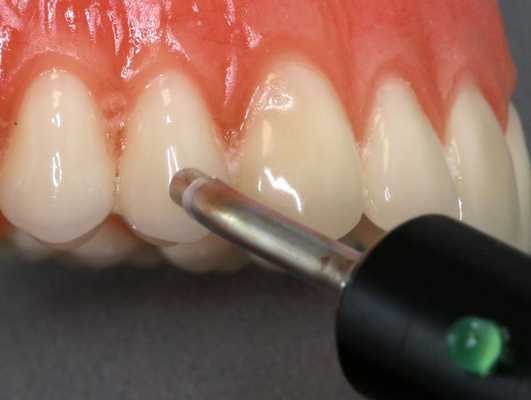

Воспаление в десне определяется с помощью пробы Шиллера-Писарева и оценивается по балльной шкале до и в процессе лечения. Состояние сосудов тканей пародонта можно оценить с помощью определения стойкости мелких кровеносных сосудов (автор — Кулаженко, ведется учет времени образования гематом в области десны при воздействии вакуума). Для этих целей также используется метод реопародонтографии, фотоплетизмографии, биомикроскопии. Для определения насыщенности тканей пародонта кислородом в последние годы применяется метод полярографии.

Диагностика периодонтита проводится на основании жалоб пациента, анамнеза заболевания, оценки общесоматического статуса, осмотра головы и шеи, полости рта, зуба, его перкуссии, зондирования и термопробы, электроодонтодиагностики (ЭОМ) и рентгенологического исследования. [10]

ЭОМ — это метод стоматологического исследования, основанный на определении порогового возбуждения болевых и тактильных рецепторов пульпы зуба при прохождении через неё электрического тока.

Наличие одного или нескольких симптомов является поводом для скорейшего обращения за стоматологической помощью, чтобы определить, насколько глубоки поражения. Измерение глубины зазора между зубом и десной является основной диагностической процедурой, которая, несмотря на простоту, позволяет достаточно точно определить глубину поражения. Для проведения исследования используется пародонтальная проба, которую помещают между зубом и десной и тем самым измеряют глубину промежутка. Результаты обследования каждого зуба записывают и получают пародонтограмму.